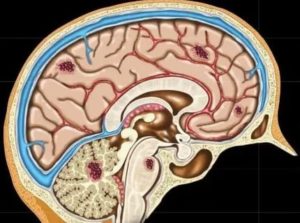

Наряду с основными симптомами, больной может чувствовать сильную головную боль. Поэтому риносинусопатию часто связывают с воспалением в головном мозге, однако это заболевание не несет для органа непосредственной угрозы. Кроме того, у больного снижается работоспособность, ухудшается сон и аппетит, появляется раздражительность и вялость.

По причине близкого расположения придатков носовых, болезнь считают патологией головного мозга, однако, это сильное заблуждение.